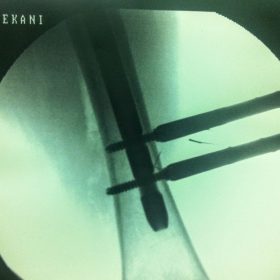

Διατροχαντήριο : Εξωαρθρικό κάταγμα, στην περιοχή ανάμεσα στο ελάσσονα και το μείζονα τροχαντήρα. Αντιμετωπίζεται χειρουργικά με ενδομυελική ήλωση τύπου γ-Nail. Δύο τομές 3 εκατοστών και 1 εκατοστού αντιστοίχως για την εισαγωγή και το κλείδωμα του ήλου μέσα στο οστό. Η μέθοδος είναι κλειστή,σχεδόν αναίμακτη,διάρκειας 30 λεπτών,με τη βοήθεια C-ARM (τηλεόρασης). Στον ασθενή παρέχεται οπτικό υλικό (όλα τα χειρουργικά στάδια) σε CD ή Στικάκι,λόγω της δυνατότητας καταγραφής του χειρουργείου από το C-ARM Ο ασθενής περπατάει άμεσα μετεγχειρητικά στις 5 ώρες μετά την επέμβαση και εξέρχεται από το νοσοκομείο σε 1 -2 ημέρες.

Υποτροχαντήριο :Εξωαρθρικό κάταγμα κάτω από τον ελάσσονα τροχαντήρα του μηριαίου οστού. Αντιμετωπίζεται χειρουργικά με ενδομυελική ήλωση τύπου Long γ-Nail. Δύο τομές 3 εκατοστών και 1 εκατοστού αντιστοίχως για την εισαγωγή και το κλείδωμα του ήλου μέσα στο οστό. Η μέθοδος είναι κλειστή,σχεδόν αναίμακτη,διάρκειας 60 λεπτών,με τη βοήθεια C-ARM (τηλεόρασης). Στον ασθενή παρέχεται οπτικό υλικό (όλα τα χειρουργικά στάδια) σε CD ή Στικάκι,λόγω της δυνατότητας καταγραφής του χειρουργείου από το C-ARM Ο ασθενής περπατάει άμεσα μετεγχειρητικά στις 5 ώρες μετά την επέμβαση και εξέρχεται από το νοσοκομείο σε 1 -2 ημέρες.